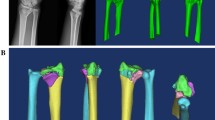

Pre- and post-operative 3D images of the distal radius were analyzed using image analysis software (BoneSimulater, Orthree, Osaka, Japan). DICOM data of CT images were imported into the software. A 3D surface model of the radius was constructed with a surface construction algorithm. The long axis of the radius was calculated from the 3D surface model of the intact part of the preoperative distal radius image. Image registration for the preoperative plan and postoperative reduction were performed using the intact part of the distal radius image. The y-axis was defined as the long axis of the radius, and the proximal direction was defined as positive. The z-axis was parallel to the orthogonal projection of a line initiating at the base of the distal ulnar sigmoid notch and continuing to the radial styloid process on a plane perpendicular to the y-axis. The radial direction on the z-axis was defined as positive. The x-axis was normal to the yz plane and the palmar direction was defined as positive. The yz, xy, and xz planes were defined as the coronal, sagittal, and axial planes, respectively. The origin of coordinates was defined as the intersection of the joint surface and the radius of the long axis on the preoperative plan image. Three reference points: (1) the radial styloid process, (2) the sigmoid notch volar edge, and (3) the sigmoid notch dorsal edge, were marked on pre- and post-operative 3D images (Fig. 7). The 3D coordinates of each reference point and the barycentric coordinates of the plane connecting the three reference points were evaluated using the 3D images of the preoperative plan and postoperative reduction.

Example images of 3D reference points. a An example image for each reference point. Left row images show the reference points in the preoperative plan image. Right row images show the reference points in the postoperative image. The light blue bar indicates the long axis of the distal radius. Red dots indicate the radial styloid process: reference point (1), the sigmoid notch volar edge: reference point (2), the sigmoid notch dorsal edge: reference point (3), and the barycentric coordinates. b An example image for 3DVT and 3DRI. The angle between a connecting line from reference point (2) to reference point (3) and a line perpendicular to the longitudinal axis of the radius was measured as the volar tilt on a 3D image in the sagittal view (3DVT). The angle between a line from reference point (1) to reference point (2) and a line perpendicular to the longitudinal axis of the radius was measured as the radial inclination on a 3D image in the coronal view (3DRI). The measured angles in the example image were 19.2° and 12.7° for 3DRI and 3DVT, respectively

In the sagittal view, the angle between a connecting line from reference point (2) to reference point (3) and a line perpendicular to the longitudinal axis of the radius was measured as volar tilt (3DVT). In the coronal view, the angle between a line from reference point (1) to reference point (2) and a line perpendicular to the longitudinal axis of the radius was measured as radial inclination (3DRI).